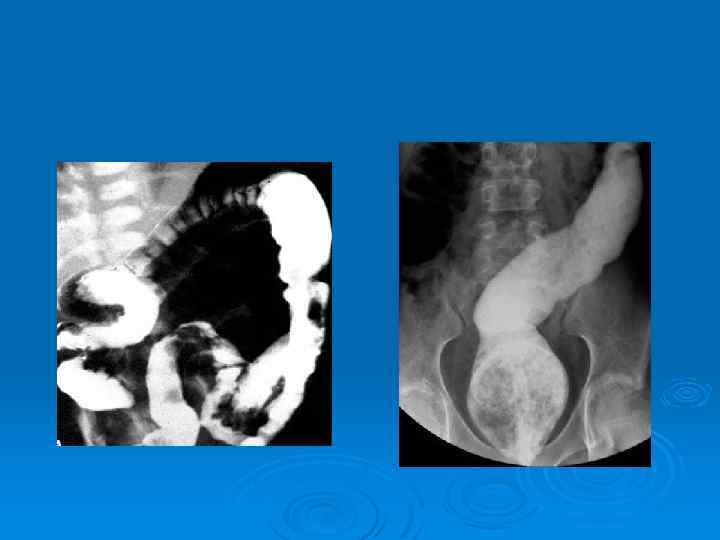

Диагностика При осмотре выявляют увеличение живота (постоянный метеоризм), иногда можно наблюдать перистальтические сокращения кишки, прощупать плотные каловые массы. Ø При пальцевом исследовании прямой кишки определяют повышение тонуса сфинктера заднего прохода, пустую ампулу спастически сокращенной прямой кишки. Ø При рентгенологическом исследовании в вертикальном положении выявляются раздутые газом петли кишечника, характерные для кишечной непроходимости. Ø

Диагностика Во время колоноскопии из-за спазма прямой кишки вначале ректоскоп продвигается с трудом, а затем он как бы проваливается в расширенную ее часть, которая всегда заполнена каловыми массами и каловыми камнями. Ø Ирригоскопия позволяет выявить зону сужения, ее протяженность и локализацию, протяженность расширенной супрастенотической зоны толстой кишки, диаметр которой обычно составляет 10 -15 см. Ø При изучении пассажа бариевой взвеси по пищеварительному тракту выявляют длительную (в течение нескольких суток) задержку взвеси в расширенных отделах толстой кишки. Ø